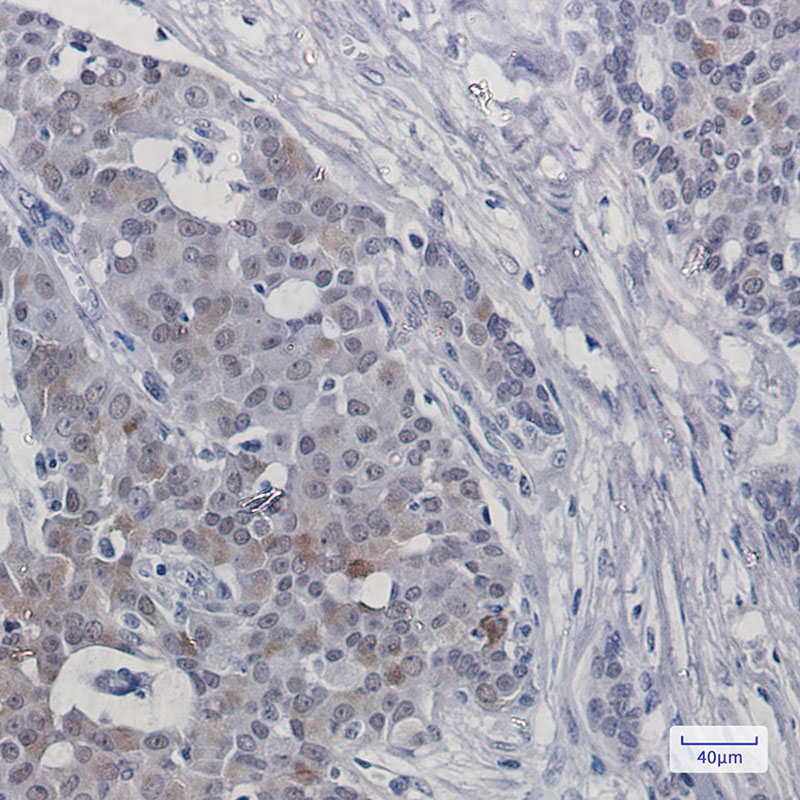

- Immunohistochemistry analysis of paraffin-embedded Human breast cancer using HTF9C antibody. High-pressure and temperature Sodium Citrate pH 6.0 was used for antigen retrieval.